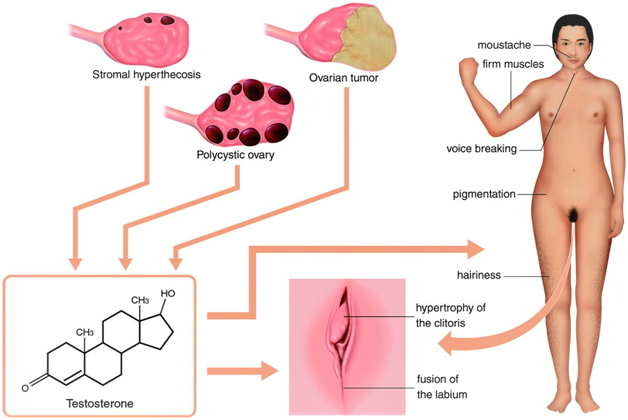

Figure 2 Hyperandrogenism in women. An excess of androgens causes hirsutism and, in severe cases, virilization. Hirsutism involves the presence of hair that does not normally appear in women, such as a mustache. Virilization includes male-pattern baldness, coarsening of the voice, a decrease in breast size, an increase in muscle mass, loss of female body contour, and enlargement of the clitoris. (The same previous source).

Excessive androgen

- Polycystic ovarian syndrome (PCOS) is the most common hyperandrogenic disorder, affecting 5-10% of all women.

- PCOS involves irregular ovulation in combination with excess androgens and with or /wo polycystic ovaries on imaging.

- Hyperthecosis, can have testosterone levels in the tumor range!

- Tumors of the ovary secrete high levels of testosterone.

The testosterone levels exceed 2.0ng/mL (200ng/dL, 8.92nmol/L) or 2.5times the upper limit of the reference range; Sertoli-Leydig cell tumors, hilus cell tumors, and lipoid cell (adrenal rest) tumors are the most common.